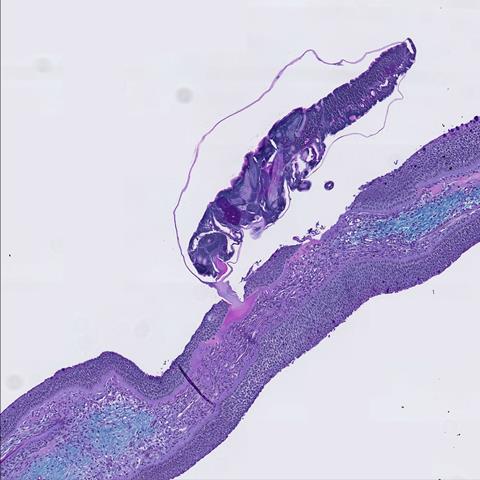

Rather than looking at the entire immune system, researchers focused on the initial site of attachment on the skin.

The study found that coho salmon trigger a strong inflammatory response within two days of louse contact. Immune cells rapidly flood the area, making it difficult for the lice to stay attached. Atlantic salmon, by comparison, show a much weaker response.

Other Pacific species like chum and pink salmon also display impressive defences, with researchers noting a high density of mucous cells on their skin. In fact, lice struggled to attach without anaesthetising the fish.